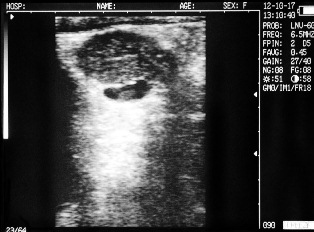

Ultrasound images of cows reproductive system, generated by a scanner Sonovet with rectal linear transducer.

Cow with calf. Deadline - 30 days